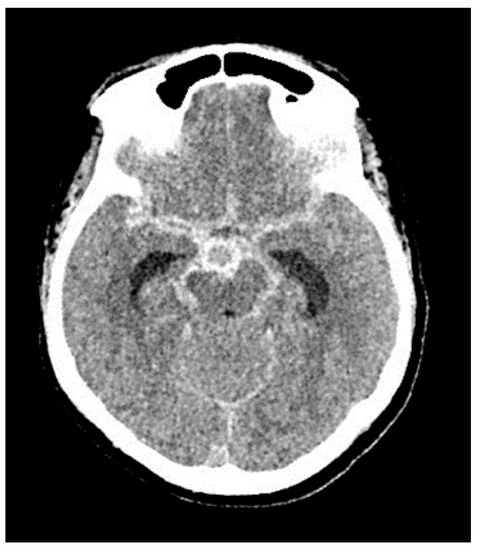

3.1. Case 1

3.2. Case 2

3.3. Case 3